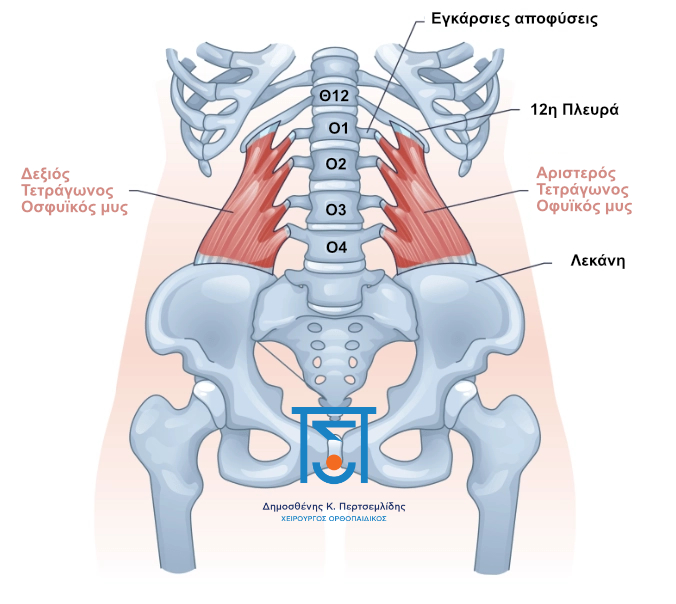

Θαμμένος βαθιά κάτω από τους παχιούς επιφανειακούς μύες της πλάτης σας, βρίσκεται ένας ορθογώνιος μυς σε κάθε πλευρά της σπονδυλικής σας στήλης που ονομάζεται Τετράγωνος Οσφυικός μυς (Quadratus Lumborum). Συνδέει το χαμηλότερο πλευρό σας (το 12ο πλευρό), τις εγκάρσιες διαδικασίες των οσφυϊκών σας σπονδύλων και την κορυφή της λεκάνης σας (το λαγόνιο άκρο).

Η κύρια δουλειά του είναι η πλευρική κάμψη (λύγισμα στο πλάι) και η ανύψωση του γοφού σου προς τα πάνω όταν περπατάς. Είναι ένας κρίσιμος σταθεροποιητής της κάτω σπονδυλικής σας στήλης.